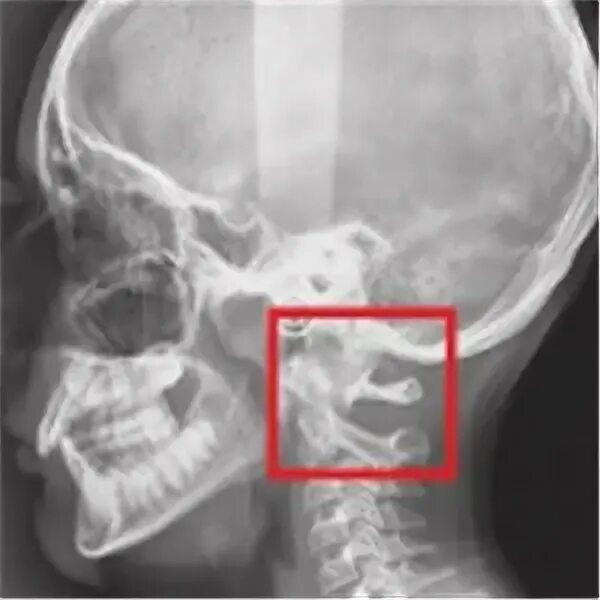

Аномалия перехода